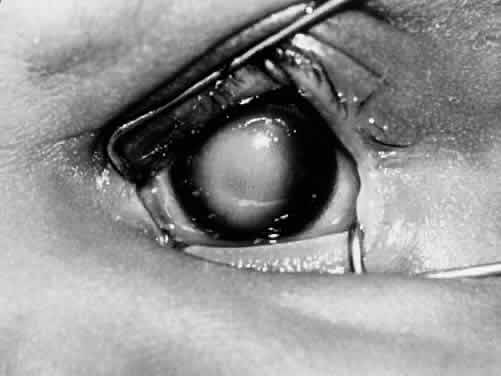

PERSISTENT HYPERPLASTIC PRIMARY VITREOUS

PHPV is frequently noted at birth or shortly thereafter as a microphthalmic eye, often with a white pupillary reflex. PHPV is therefore a part of the differential diagnosis of retinoblastoma. Although 90% of cases are unilateral, a Mittendorf's dot or other developmental anomaly of the anterior vitreous may be observed in the contralateral eye.169,170 Elongated ciliary processes may be seen, and the anterior chamber may become progressively shallow. Late complications include swelling of the lens with cataract formation, as well as pupillary block with angle-closure glaucoma. If not treated, this condition may progress to phthisis bulbi. PHPV is caused by an abnormal regression and hyperplasia of the primary vitreous (see Part 1). Retinal astrocytes and glial cells from the optic nerve head are responsible for the hyperplastic component of PHPV. These cells may also be the source of the fibrous component of the PHPV membrane.171,172 Adipose tissue, smooth muscle, and cartilage may be found within the retrolental plaque.173